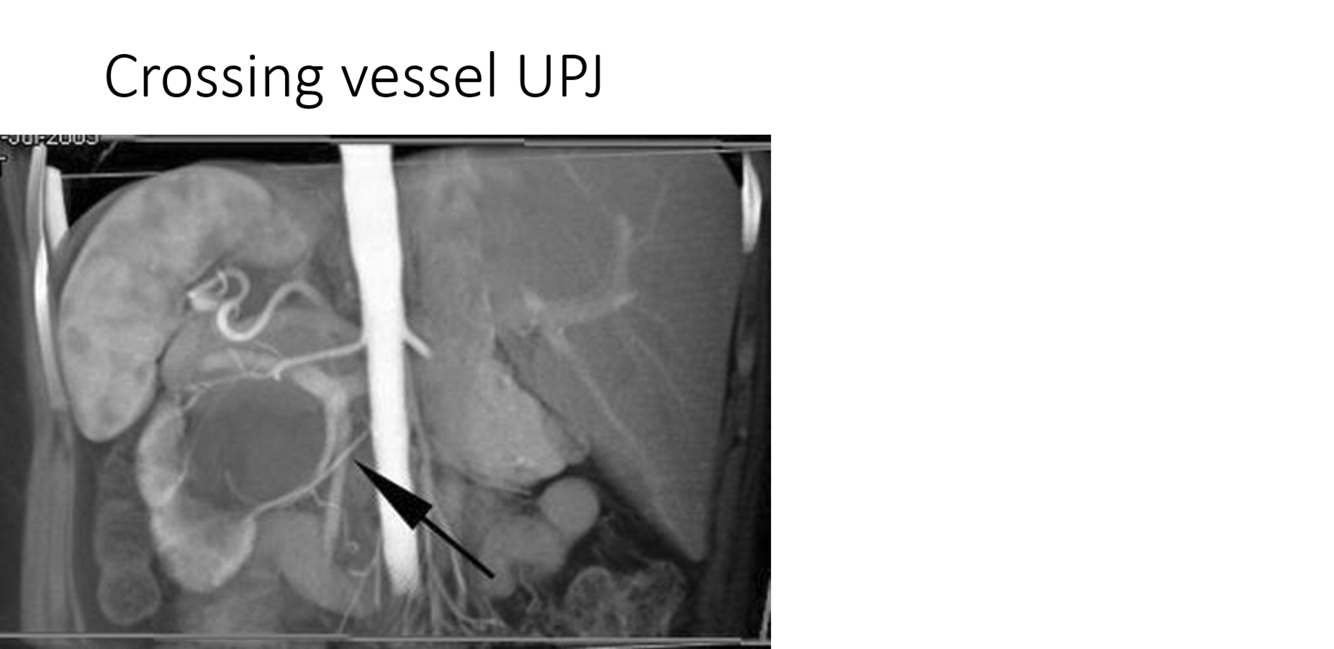

UPJ crossing vessel